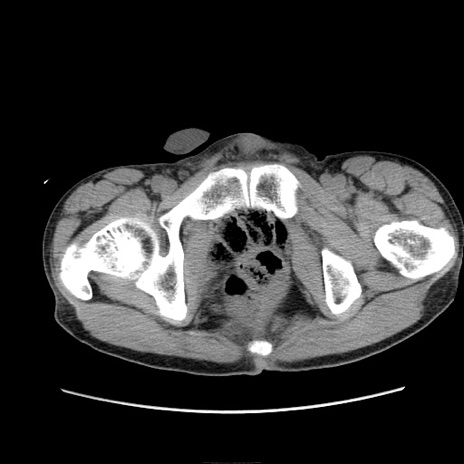

症例11(横断像)

【症例】 60歳代男性

【主訴】 下腹部痛

【現病歴】 本日夜中より下腹部痛の症状認め、受診。

【既往歴】 膀胱癌(膀胱全摘+尿管皮膚瘻術) 、胃癌術後

【身体所見】 BT 35.3℃、PR 58/min、BP 136/98mHg、腹部平坦、軟、腸蠕動音±、ストマ留置あり、左上腹部~正中部に圧痛あり、反跳痛なし。

【データ】WBC 5100、CRP0.01